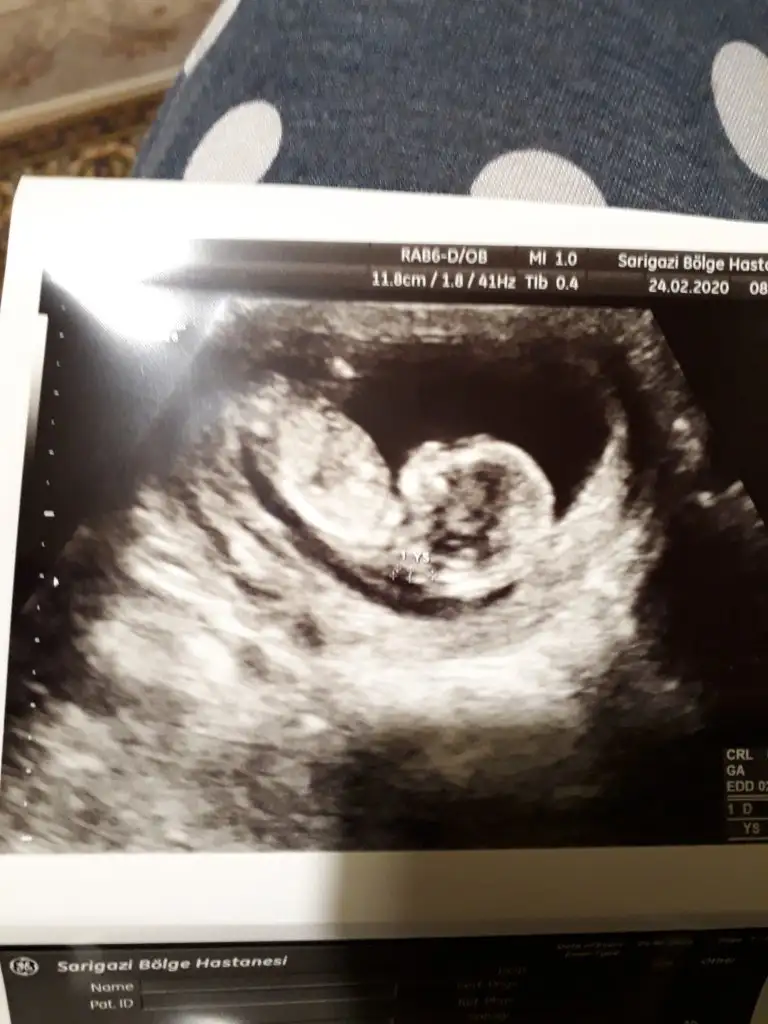

Dr + tam nuba denk getirmiş başka usg varmı12+4 banada yorumlarmisijizIkra meyra

Baska yokDr + tam nuba denk getirmiş başka usg varmı![]()

Bu göre kız ama tutmayabilir tekrar usg olursa paylaşın .usteki 12+3 usg de kafa yapısı kız gibi ama nub göremiyorum .13+ usg olursa paylaşırsınızBaska yok![]()